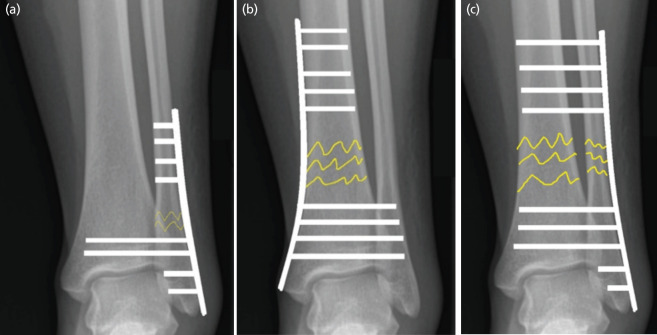

Fibula Pro-tibia or Tibial Pro-fibula Dilemma: Order Defines Meaning.